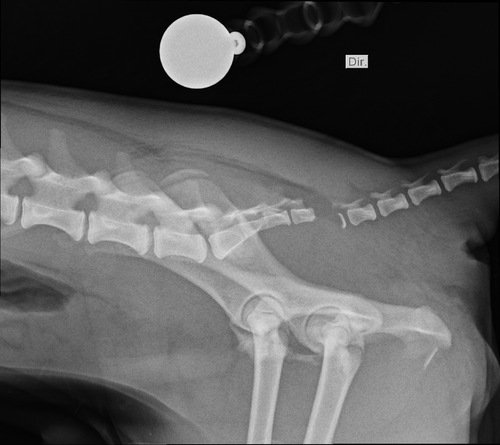

Tatu fugiu e foi atropelado, o motorista fugiu e não prestou socorro, ele teve 3 fraturas e terá que a realizar 3 cirurgias, fora exames e a internação na clínica  ver tudo

Tatu fugiu e foi atropelado, o motorista fugiu e não prestou socorro, ele teve 3 fraturas e terá que a realizar 3 cirurgias, fora exames e a internação na clínica